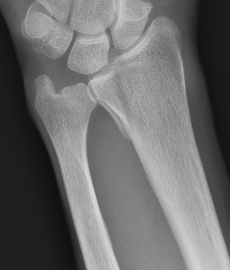

Colle's Fracture

- distal radial fracture with dorsal displacement

Smith's Fracture

- distal radial fracture with volar displacement

All fractures should be reduced initially and reassessed

- conscious sedation

- 2 minutes of traction / reduction of deformity

- backslab / elevation in gallows

- re-xray

CT for further evaluation of articular congruency